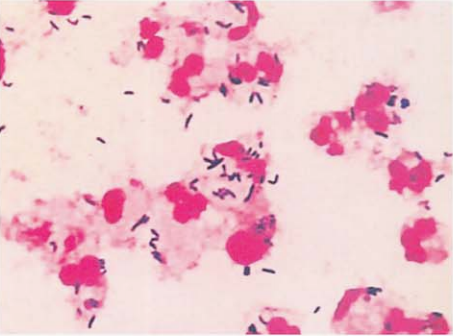

革兰阳性杆菌,V形、栅栏状,单个或成双排列(图 6)。痰标本直接涂片查见革兰阳性杆菌(图 7)。血培养阳性培养物直接涂片查见革兰阳性杆菌(图 8)。

图 7 痰标本中纹带棒杆菌的镜下形态(革兰染色)

图 8 含树脂血培养瓶涂片(革兰染色)